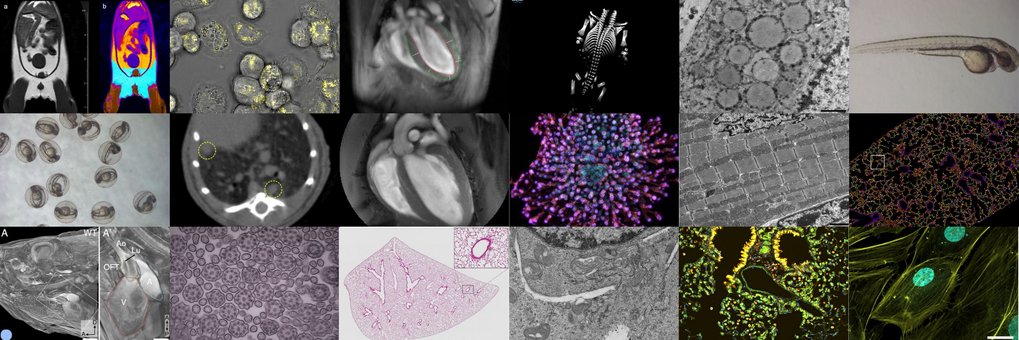

Um exzellente Forschungsergebnisse hervorbringen zu können, bedarf es nicht nur herausragender Wissenschaftler, sondern auch eines effizienten Systems aus wissenschaftlichen Services, die die Arbeit der Abteilungen mit modernsten Technologien gezielt unterstützen. Beim Max-Planck-Institut für Herz- und Lungenforschung in Bad Nauheim sind dies die Servicegruppen: